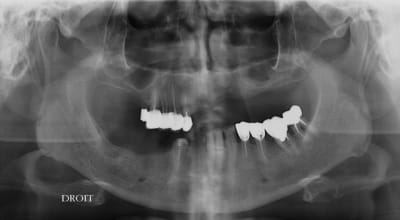

le but c'est de refaire la bouche de la dame, il lui reste fort peu de dent et elle m'a pour le moment posé une limite de budget qui me permet de faire le bas.

en haut j'ai déposé un bridge de 4 dents,(17/16/15/14) et j'ai fait une "augmentation" du sinus par la racine mesiale de 16, (avec un balloon)un comblement de sinus par fenetre latérale n'etant pas envisageable pour le moment.

en bas extrac 33/34

dans 3 semaines je pense poser 7 à 9 implants et peut etre mise en vitrine immediate (pas sur)